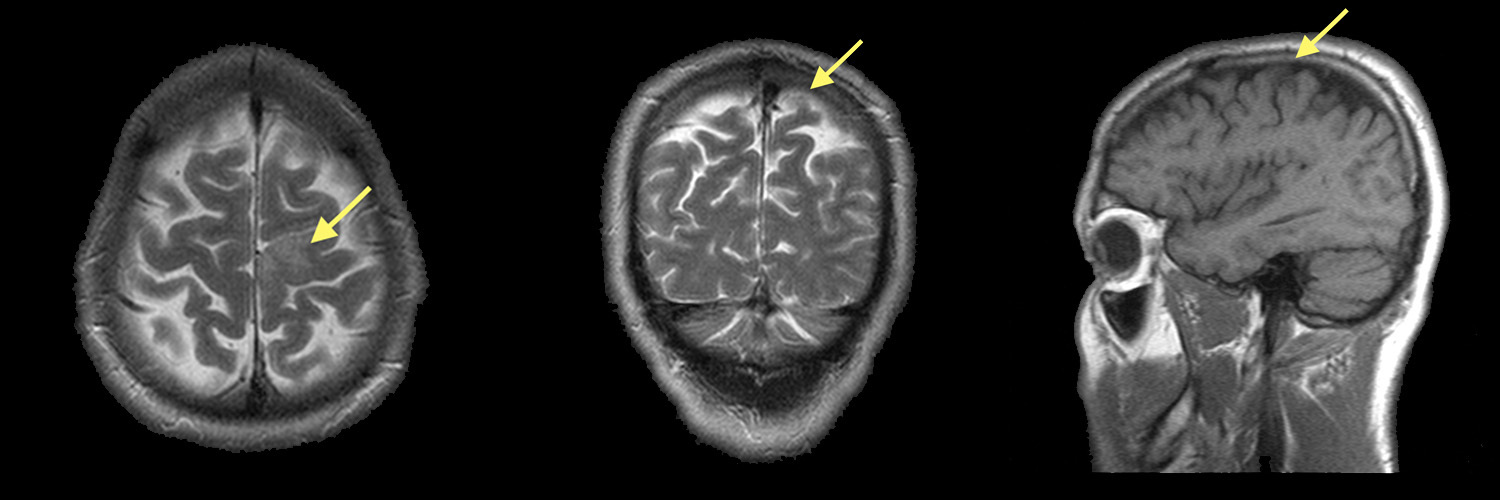

Медицинские аспекты и диагностика субдуральной гигромы мозга